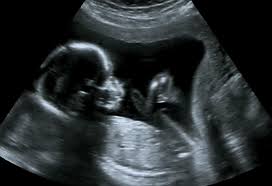

The median age at death is now the mid-50s compared. Down syndrome varies in severity among individuals causing lifelong intellectual disability and developmental delays. You may have an ultrasound between 18 to 20 weeks to evaluate dates a multiples pregnancy placenta location or complications.

20 Weeks Pregnant Ultrasound Procedure Abnormalities And More

The 20-Week Anatomy Scan May 2017.